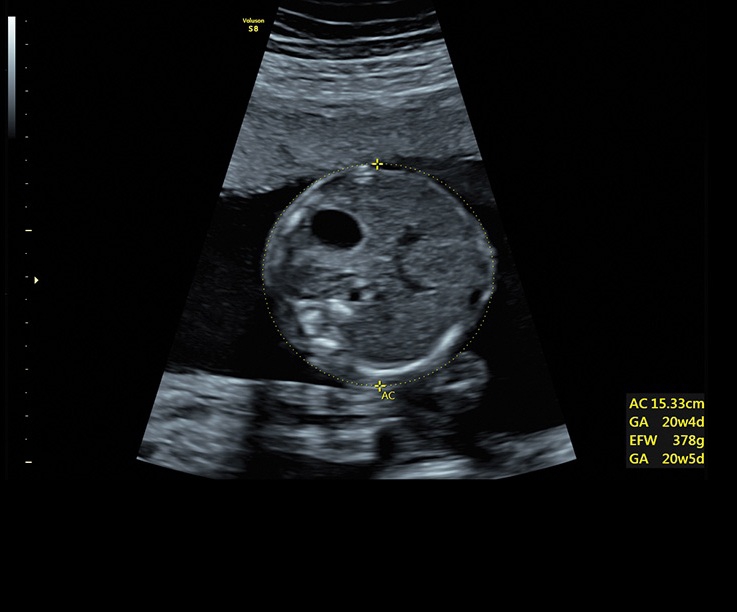

• Технология автоматической фетометрии в 2D режиме (SonoBiometry): Эта технология позволяет автоматически измерять бипариетальный размер, окружность головы, окружность живота, длину бедра и плеча плода, обеспечивая точные и надежные измерения.

• SonoBiometry (автоматическое измерение BPD, AC, HC, HL, FL)